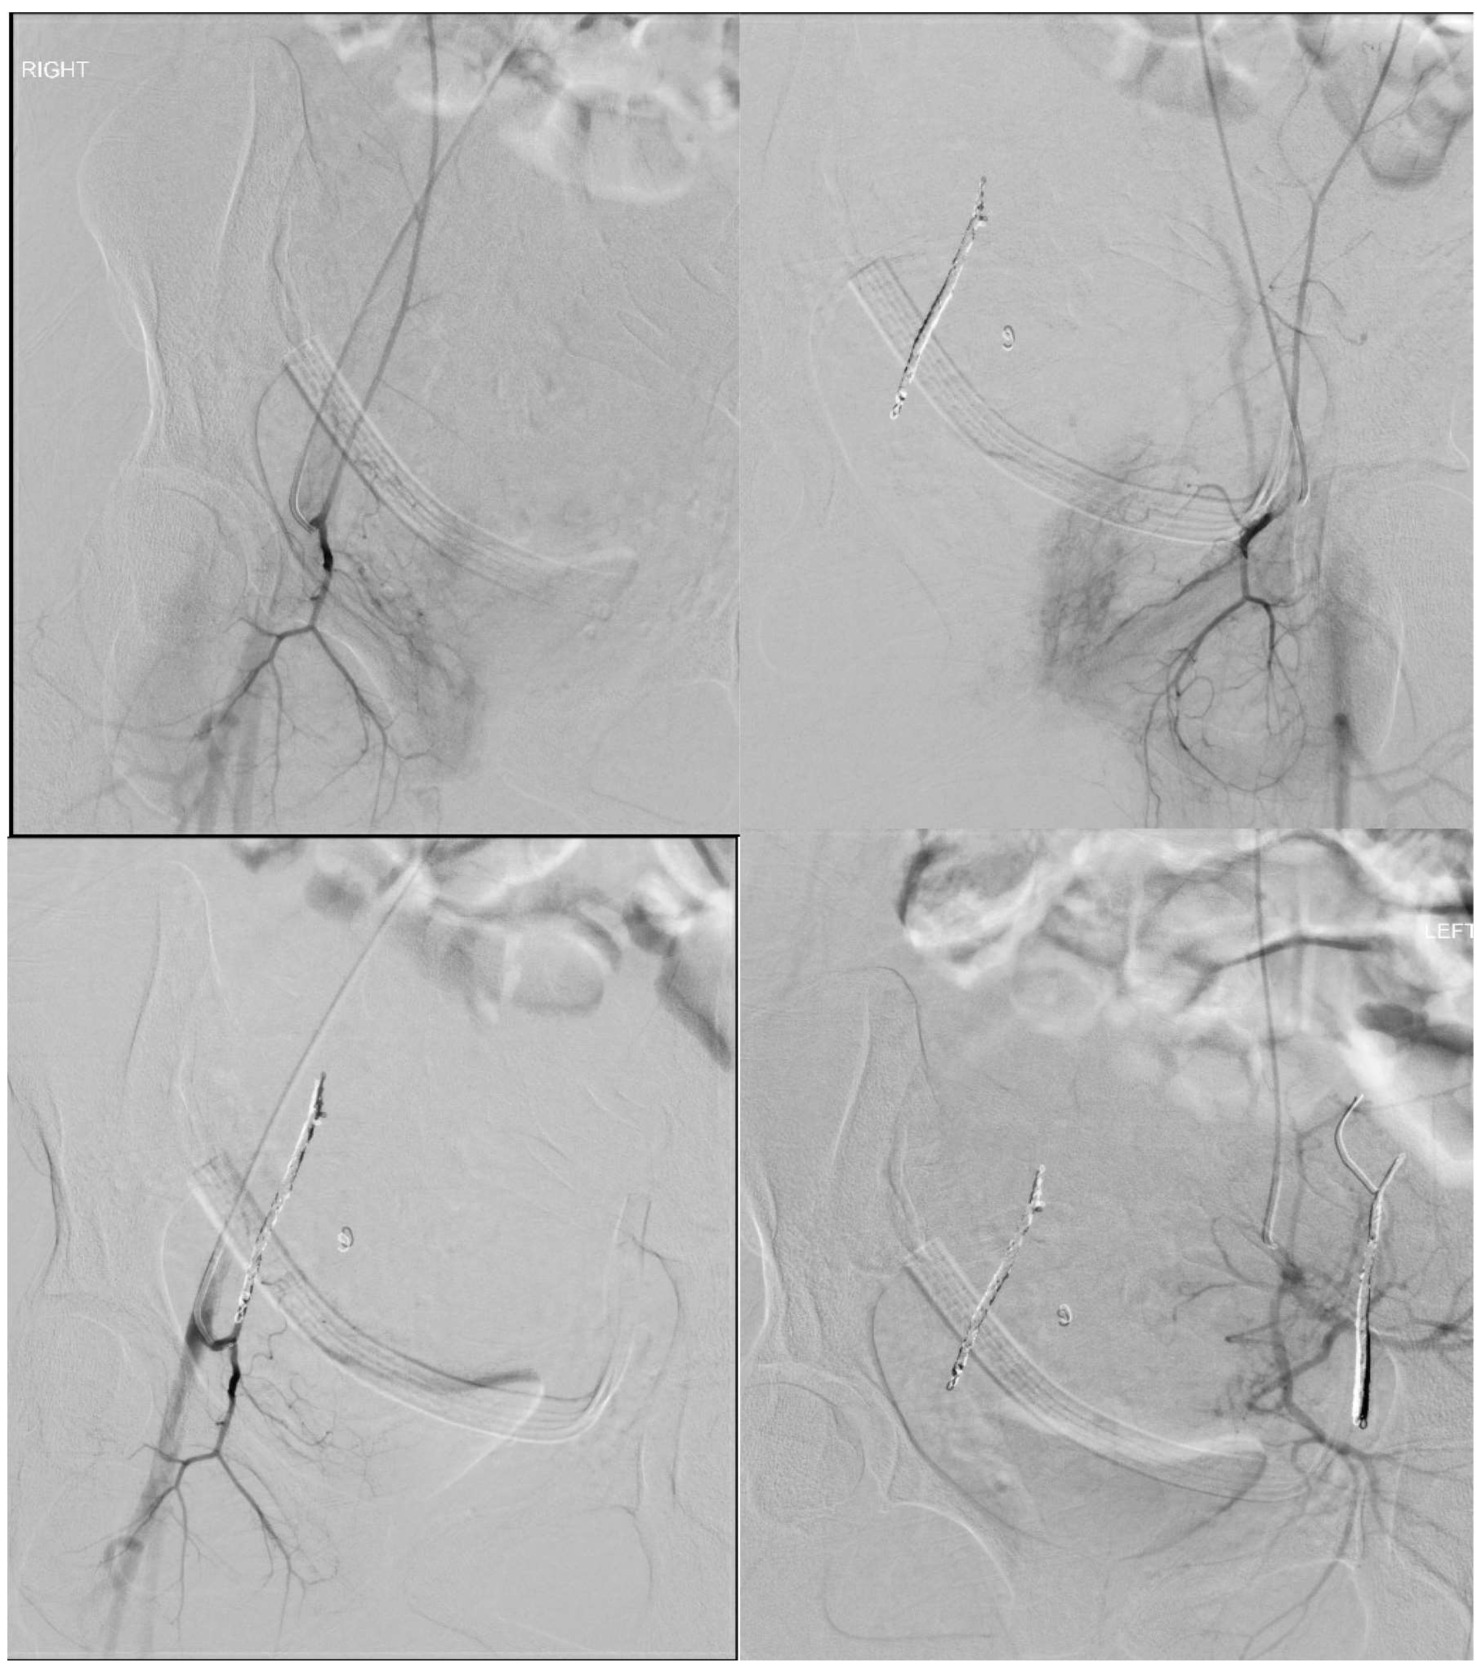

On postoperative day one, the patient’s hemoglobin was noted to be 6.5 g/dL, a significant decrease from her admission hemoglobin of 10.8 g/dL. She had symptomatic acute blood loss anemia endorsing dizziness but remained normotensive and non-tachycardic. A unit of packed red blood cells was administered. The patient initially denied abdominal pain but later reported worsening discomfort. On physical exam, her abdomen was distended and tender to palpation in all quadrants. A CT scan demonstrated hemoperitoneum with a moderately large amount of blood noted along the right side of the uterus. High attenuation infiltrative changes were noted within the anterior pelvic wall musculature. On post contrast imaging, there was pooling within the anterior abdominal wall musculature concerning for active bleeding (Figure 1). Although she remained hemodynamically stable, her worsening abdominal exam prompted a return to the operating room for an emergent exploratory laparotomy due to concern for intrabdominal hemorrhage.

Shortly after transferring the patient to the recovery area, active bleeding was noted at the surgical site, saturating the dressing. Frank red blood was seen in the JP drain. Interventional radiology was consulted to evaluate for possible intravascular embolization. Multiple sites of both the left and right inferior epigastric arteries were identified as sources of active bleeding on CT angiography. Successful coil embolization of bilateral inferior epigastric arteries was performed. Figure 2 demonstrates active extravasation of contrast prior to embolization in comparison to post embolization arteriograms. She received a total of three units of packed red blood cells with and estimated total blood loss of 2000 cc. Despite these losses, the patient remained hemodynamically stable with a normal coagulation profile. The JP drain was removed prior to discharge.